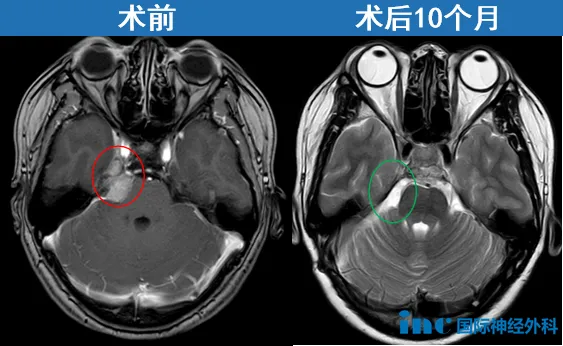

52岁的钟女士也是在体检中发现脑膜瘤。随后一年,她辗转多家医院,却屡屡被告知“手术风险太高”、“后遗症难料”、“难以全切”。焦虑让她夜不能寐,全家都笼罩在阴霾之中。直到伽马刀治疗效果不佳,她最终毅然选择手术,迎来生命的转机。点击阅读:体检查出脑瘤可能是误判吗?无症状,治还是不治?